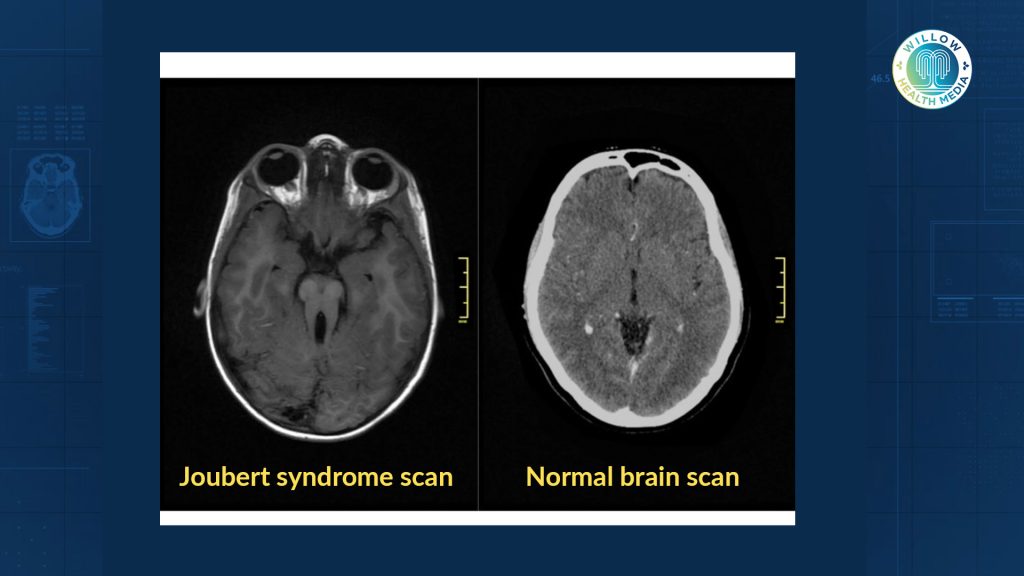

Joubert syndrome is a genetic condition caused by mutations in more than 30 known genes. It primarily affects brain development, especially the area responsible for balance and coordination. The telltale sign is a brain scan showing what doctors call the “molar tooth sign.”

In Joubert syndrome, the midbrain, which controls vital motor functions, doesn’t form correctly. This causes a ripple effect across the body.

“The brain is a big and serious organ that controls everything,” Dr Mutinda adds. “In the specific case of Joubert’s syndrome, the midbrain is not formed as it should be. And therefore, the functions of that part of the brain are all affected. This includes balance, inability to coordinate, and the way they are moving.”